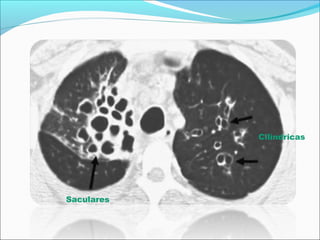

DIAGNOSTICO DE IMAGEN

-Relación

broncoarterial

>1-1,5

-Falta de

afilamiento de

los bronquios

-Visualización

de bronquios a 1

cm de la pleura

Saculares

Cilíndricas

Varicosa

TACAR